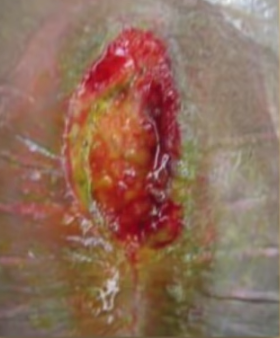

What’s first line tx of anal fissure? (3)